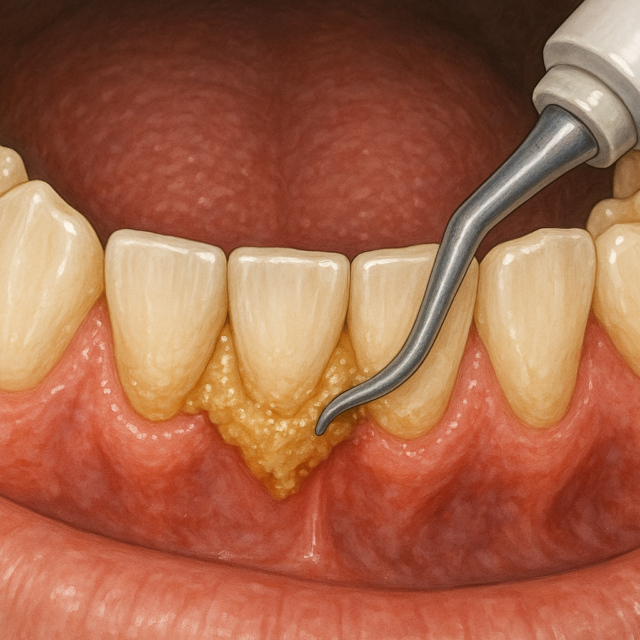

「歯石を取るだけで終わりじゃない。歯周病予防の本当のゴールとは?」

目次 1. はじめに:なぜ多くの人が“歯石さえ取れば大丈夫”と思ってしまうのか …